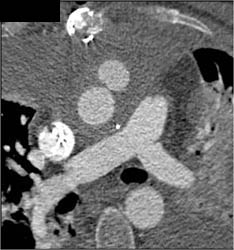

3 Patent Venous Grafts